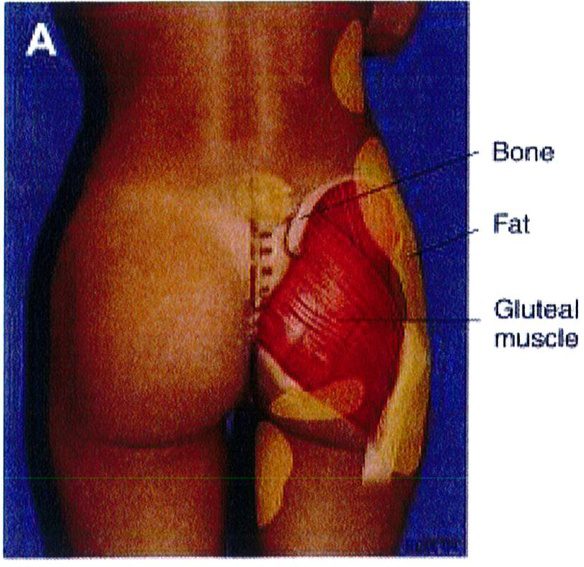

Sự tương tác của 4 tổ chức này mang lại cho vùng mông một hình dáng đặc trưng cụ thế (hình 1A). Để đơn giản hóa chủ đề phức tạp này, hãy tưởng tượng cơ thể là một cấu trúc có thể tháo rời. Khi tách cơ ra thì phần còn lại là khung xương, mỡ và da, có thể gọi chung là khung (Hình 1B).

Hình 1. (A) Hình thể toàn bộ vùng mông phụ thuộc vào khung xương, cơ mông lớn, vị trí và lượng mỡ dưới da, độ căng của da. (B) Khung mông, với cơ môna lớn đã được tách ra.

Over rall Buttock Shape : Hình thể toàn bộ vùng mông Gluteal muscle: Cơ mông Gluateal muscle(gluteal shape): Hình dạng cơ mông Frame: Khung